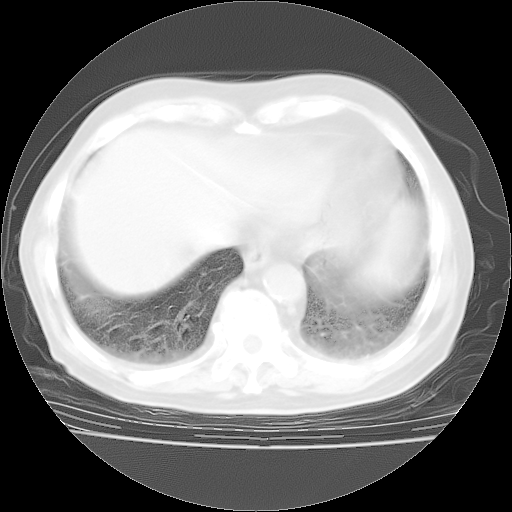

4月28日肺部CT——再次出现类似去年5月9日——透光度降低,“间质性”改变。

4月28日肺部CT——再次出现类似去年5月9日——磨玻璃样、间有“粟粒样”改变。

4月28日肺部CT

个人阅读4.14日肺部CT平扫:纵隔窗无异常,但肺窗示:双下肺内、后基底段有片絮状侵润影,部位以后基底段为著,以间质改变为主,呈急性肺泡炎征像,和首次住院影像学有相似之处。仅是个人读片,明日请相关专家再读片哈。其它建议同上。

1、108#的是4月14日的胸部CT(发此贴时还没看着28日的CT)。14日的胸部CT其实已经出现改变(如108#所述),个人认为28日的胸部CT除纵膈窗疑似有双侧胸膜增厚或少量胸积液(可行胸部B超明确)外,与4月14日对照病变有所加重;2、已经给予“异烟肼、利福平、乙胺丁醇”抗痨治疗?如果是,甲强龙80mg可缓慢减量;如果环磷酰胺已停用,暂不使用;3、中性粒细胞92%,明显升高,目前体温情况?注意合并细菌感染可能,使用左氧氟沙星情况下,是否联用B-内酰胺类抗菌药物?另外是查免疫全套非风湿全套。

今请临免主任会诊后认为:4月14日胸部CT已有双下肺间质性改变。患者病情复发多系激素减量过快不正规所致。目前甲强龙80mg/日,一周后酌情开始减量,不易过快。环磷酰胺若已停用,暂不使用。他同意目前抗菌药物使用,但应考虑是否加用B-内酰胺类抗菌药物(中性细胞明显增高);2、结核复发目前依据不足;3、若免疫全套各项指标正常,考虑多系特发性肺间质炎可能大。4、加强支持,并注意保护胃黏膜。

今上午去请教了临免、呼吸主任:1、介绍病史和阅读系列胸部CT一致认为:患者肺结核不考虑,仍为肺间质纤维化,目前处于急性肺泡炎阶段。2、若仍发热,可将甲强龙增至:80mg Bid静滴,同时鉴于中性增高,合并细菌感染可能,继续左氧氟沙星治疗,再联用B-内酰胺抗菌药物,如头孢哌酮--舒巴坦;3、停用抗痨药;4、目前甲强龙每日剂量160mg ,体温正常后再酌情减量;目前暂不用免疫抑制剂;4、不建议使用免疫增强剂等;5、加强支持治疗,鼓励患者进食;5、注意随访肝、肾功及血常规情况;6、因患者目前激素用量较大,加用胃黏膜保护剂,防止消化道出血可能。